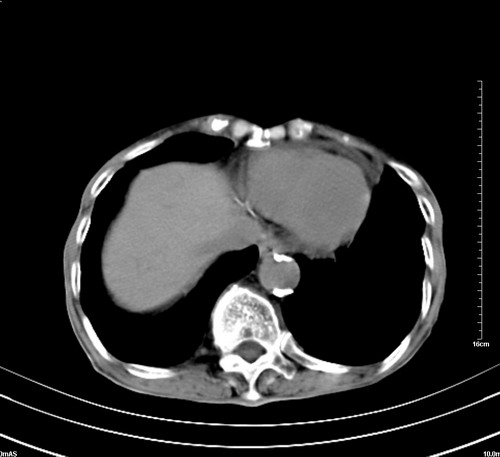

病人,女,79岁,主要因腹疼二月入院,彩超,肝,胆,脾,未见异常,胸透上消化道造影未见异常,化验白细胞增高,内科医生让做胸部ct检查,因为熟人多做了腹部(外科会诊考虑胆囊炎).现ct片如下请假各位战友.

1 气管旁、隆突下淋巴结明显肿大,肝左叶外侧段低密影,都考虑转移。

2 肝右后叶下段明显增大,片状低密影,但因各种伪影显示不佳,不排除病变。

肺癌,纵隔淋巴结转移,肝左叶病变考虑为转移病灶。

后中纵隔团块影,伴气管、食道受压移位,首先考虑转移瘤,肝s5段低密度灶。建议增强检查,另外其结肠是否有问题请提供,右肺部分肺叶局限含气增多,考虑局限肺气肿。

后中纵隔团块影,伴气管、食道受压移位,首先考虑转移瘤,肝表现同11773。